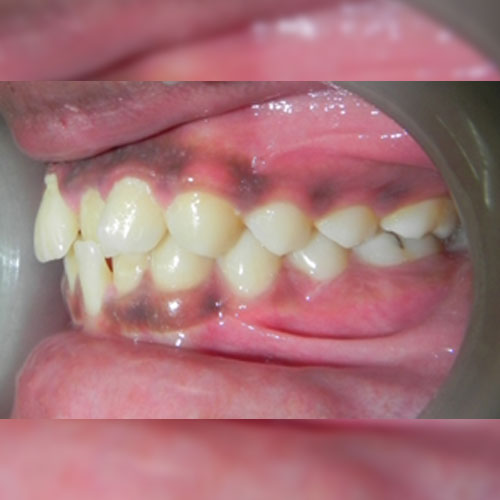

Smile Transformations

Real Patient Smile Transformations